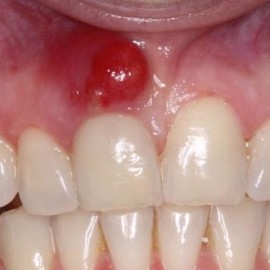

Encías sanas, cavidad bucal contenta

Unas encías sanas te permiten evitar esa apariencia inflamada y rojiza en la boca que podría avergonzarte al sonreír, además del dolor que ocasiona esta condición y el sangrado que produce al cepillarnos. Debes saber que una de las principales causas de la pérdida de dientes es la enfermedad en las encías o gingivitis. Pero Read More